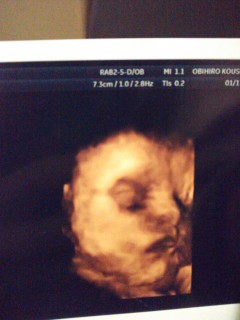

久しぶりしっかりハッキリお顔を見せてくれました!! 37w1d。 2400gの女の子です(*^^*)